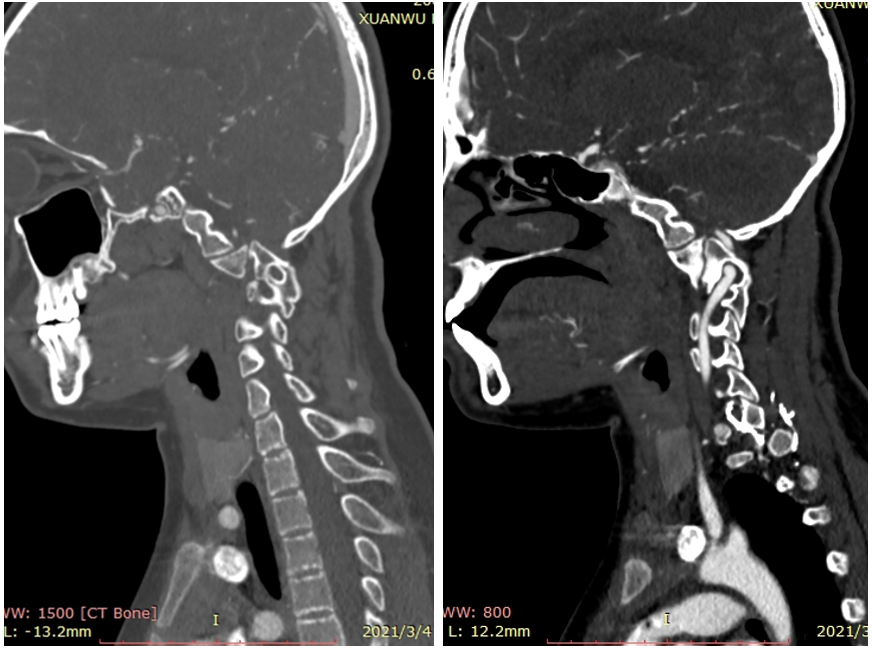

女,13岁,154cm,57kg

• 6个月前病人出现颈部活动受限,3个月前出现左手力弱

影像资料:

诊断:

• 齿状突小体

• 寰枢椎脱位

治疗:

• 后路关节松解寰枢椎复位内固定融合术

• 前路关节松解,后路寰枢椎复位内固定融合术

• 前路TARP技术

• 前路齿状突切除,后路内固定术